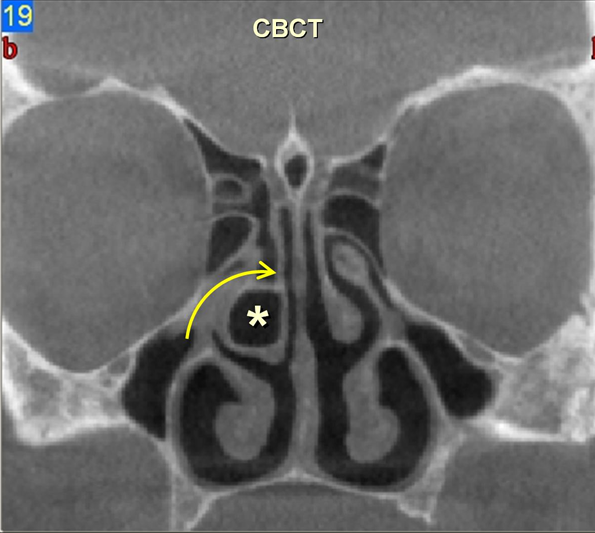

It is important to mention an emerging new technique: the cone-beam CT (CBCT). A CBCT scanner utilizes a 2D flat panel detector, and it can acquire the image of the whole volume in a single rotation around the patient. The scanning software collects the data and reconstructs it by a mathematical algorithm, producing 3D images. This method uses ten times less ionizing radiation than conventional CT, while provides all the same information. Length that can be imaged by CBCT is approx. 5-16 cm; however, C-arm equipments used in interventional radiology are also based on the cone-beam principles. CBCT’s advantages are the lower cost and smaller size, which make this technique increasingly important. CBCT can be used to visualize anatomical detail of paranasal sinuses, in dental imaging and implantology.

Paranasal sinus CT plays important role to assess more complicated, recurrent disorders. By noncontrast series, thin cortical bones, bony destruction and air-fluid levels, opacification of the sinuses can be determined. CT is of great value for determining anatomic landmarks and OMC variants. This information is of vital importance to the ENT-surgeon. Noncontrast CT allows rapid and detailed evaluation of facial bones including paranasal sinuses. Contrast administration is mandatory in soft tissue evaluation.

3. image: Paranasal sinus examination, coronal reconstructions (right panel: cone-beam CT; left panel: MDCT). Concha bullosa(asterisk) with ethmoidal infundibulum narrowing (arrow). Cone-beam CT and MDCT information correlates almost 100 %.